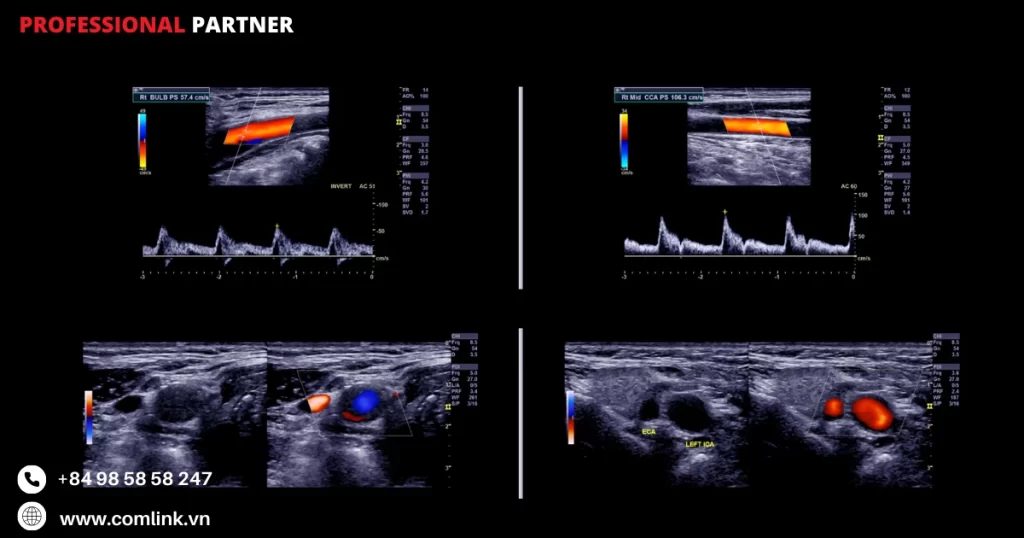

Máy quét Doppler màu

Máy quét Doppler màu là một thiết bị y tế nâng cao chất lượng hình ảnh siêu âm bằng cách hiển thị thông tin về dòng máu trong cơ thể.

Điều này giúp xác định các vấn đề về tuần hoàn máu, như sự suy thoái hoặc rối loạn tuần hoàn.

Cách hoạt động của máy quét Doppler màu

- Máy quét Doppler màu hoạt động bằng cách sử dụng nguyên lý Doppler để phát hiện và hiển thị thông tin về dòng máu trong cơ thể.

- Khi sóng siêu âm được phát vào cơ thể, máy quét sẽ nhận lại sóng phản xạ từ dòng máu.

- Dựa trên sự thay đổi tần số của sóng phản xạ, máy quét sẽ tính toán vận tốc và hướng chuyển động của dòng máu, từ đó hiển thị thông tin về tuần hoàn máu trên màn hình.

Lợi ích của việc sử dụng máy quét Doppler màu

- Xác định các vấn đề về tuần hoàn máu: Máy quét Doppler màu cho phép xem trực tiếp thông tin về dòng máu trong cơ thể, giúp xác định các vấn đề về tuần hoàn máu như suy thoái hoặc rối loạn tuần hoàn.

- Đánh giá hiệu suất tim: Thiết bị này cho phép xem thông tin về dòng máu trong tim, giúp đánh giá hiệu suất tim và xác định các vấn đề liên quan.

- Hướng dẫn can thiệp điều trị: Với thông tin về dòng máu được hiển thị trực tiếp, máy quét Doppler màu có thể hướng dẫn can thiệp điều trị, giúp cải thiện tuần hoàn máu và điều trị các vấn đề liên quan.